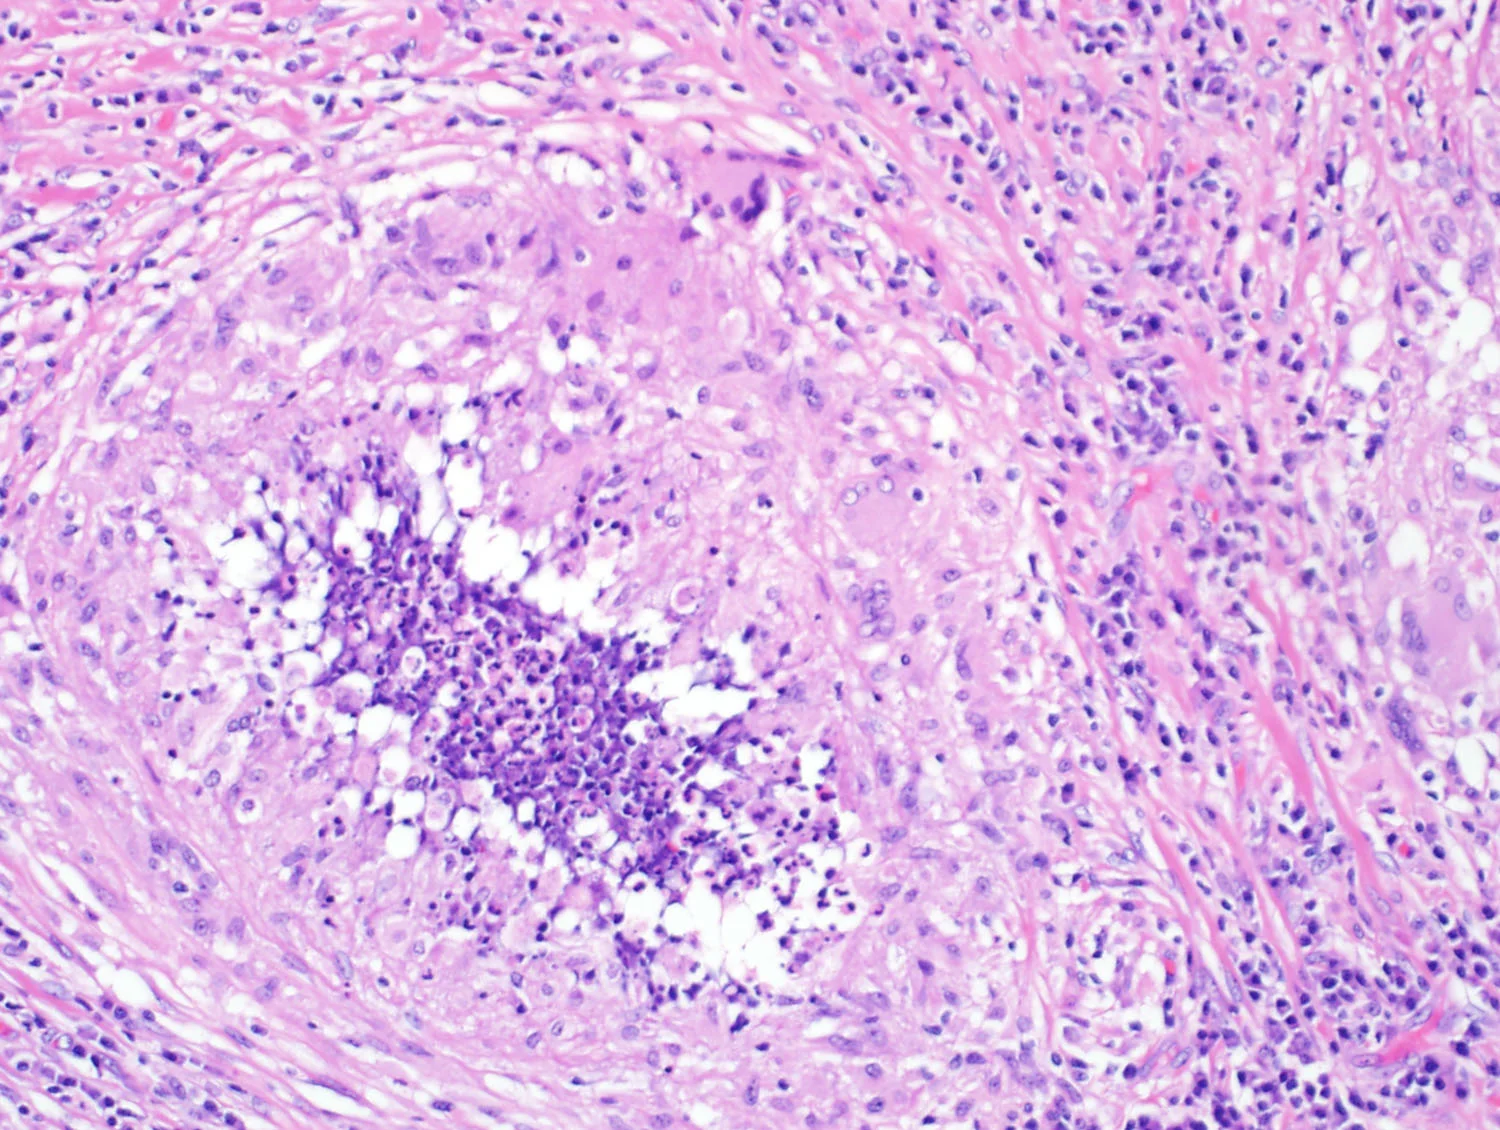

Poorly formed granuloma with a giant cell. Note the location of the granuloma. Near the bronchovascular bundle and in the interstitium (as opposed to the airspace).

Poorly formed granulomas or giants cells in an interstitial location (it is possible to make a diagnosis of CrHP without giant cells, however it is very difficult)

Poorly formed granulomas or giants cells in an interstitial location

Poorly formed granuloma

Giants cells in an interstitium

Interstitial granuloma